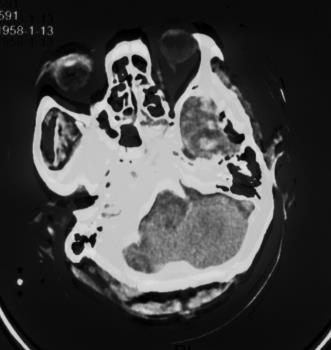

复阅2018年5月9日CT片:左额颞部开颅术后改变,部分颅骨缺如,左颞部脑组织见气体影,双侧额叶及右侧小脑见斑片状高低混杂密度影,大脑镰旁见线状致密阴影,右枕骨骨质断裂。提示左额颞部开颅术后改变,部分颅骨缺如,左颞部脑组织积气,双侧额叶及右侧小脑挫裂伤,蛛网膜下腔出血,右枕骨骨折。

图6-8,2018年5月9日 CT片,左额颞部开颅术后改变,部分颅骨缺如,左颞部脑组织积气,双侧额叶及右侧小脑挫裂伤,蛛网膜下腔出血,右枕骨骨折